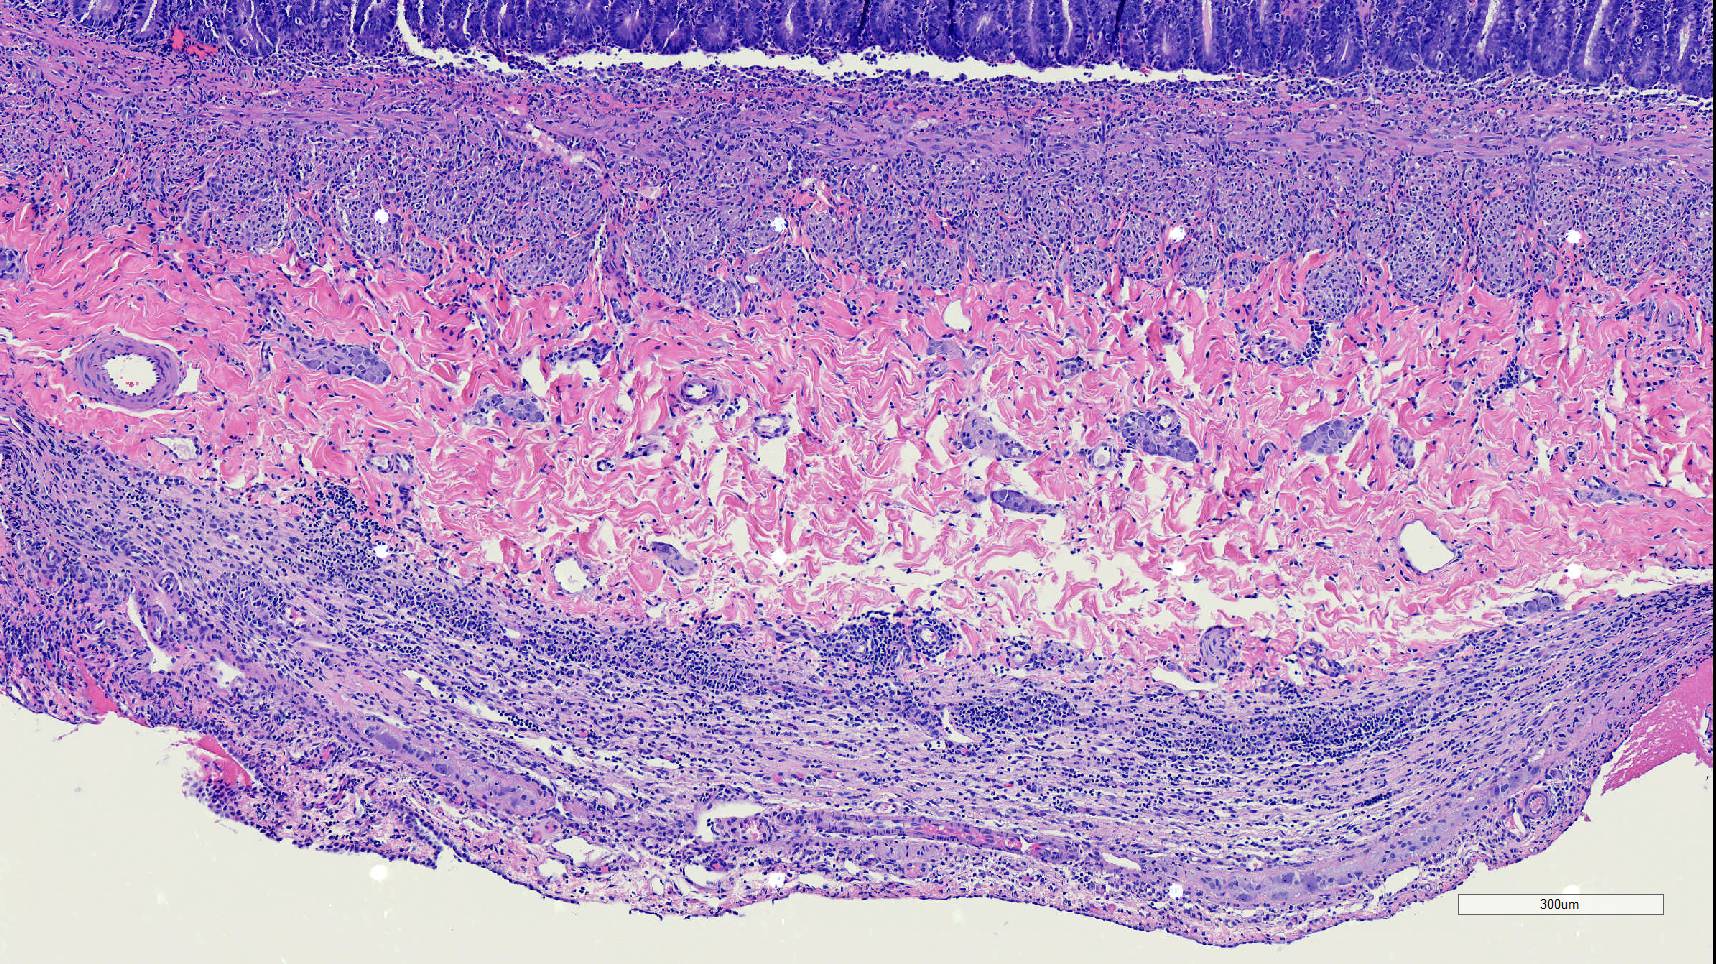

Microscopic Description:

Duodenum, jejunum and ileum: Diffusely throughout the sections, there is partial to complete loss of the leiomyocytes of the outer and inner muscularis, which are multifocally replaced by loose fibrous connective tissue (fibrosis). The remaining smooth muscle is infiltrated by large numbers small and intermediate lymphocytes, few macrophages and neutrophils. The same inflammatory infiltrate is present throughout the muscularis mucosae. Remaining leiomyocytes have pale, frequently vacuolated cytoplasm. In the submucosa, muscularis and serosa there are small to moderate numbers of perivascular lymphocytes. Small lymphocytes, and infrequently neutrophils, surround or infiltrate the myenteric and submucosal ganglia, though neurons do not exhibit degenerative changes. The lamina propria contains a markedly increased number of lymphocytes, plasma cells and a mildly increased number of eosinophils. The epithelium is diffusely overlain by myriad bacterial rods. The serosa is mildly expanded by increased clear space (edema) and is lined multifocally by markedly hypertophied mesothelium. In the stomach a similar process is observed but restricted to the outer aspect of the muscularis with a patchy/multifocal distribution and sparing of the muscularis mucosae. (section not submitted).

Duodenum, jejunum and ileum: Severe, diffuse, chronic lymphocytic leiomyositis with severe muscularis atrophy; marked, diffuse, chronic lymphoplasmacytic enteritis.

Microscopic findings reported for this condition consist of mild to marked mononuclear infiltrate, myofiber degeneration and fibroplasia or fibrosis centered within the muscularis propria of the stomach, small and large intestinal wall with the jejunum being the most severely and chronically affected segment.7,15 In early lesions the inflammation and smooth muscle degeneration are segmental, random between the outer and inner muscularis layers and sparing of the muscularis mucosae.15 Concurrent cecal involvement leading to impaction has also been described.5 Consistent histologic findings included T-lymphocyte inflammation within the muscularis propria with relative sparing of the mucosa, submucosa and neural plexuses.14 In one case report the inflammatory infiltrate was predominantly of B-lymphocytes and featured extensive angiogenesis.6 Leiomyocytes appear to be the target of the inflammation given the presence of various stages of degeneration leading to complete myofiber loss in chronic stages of the disease. Superficial inflammation is a frequent secondary finding in CIPO and has been associated with bacterial overgrowth, which were changes observed in this case.6 Neuropathy has not been a feature in most reports of canine CIPO. Inflammatory cells obscuring the myenteric and submucosal plexuses in this case were considered an extension from the neighboring inflammation as no degenerative changes were observed in the neurons. Myenteric ganglionitis has, however, been reported occurring concurrently with leiomyositis.10

Small intestine: Leiomyositis, lymphocytic, chronic, diffuse, severe, with marked smooth muscle loss and fibrosis.